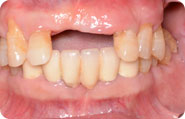

口腔情况:张先生上牙掉的没剩几颗,装的假牙咬合力不好,已经十年不识肉滋味了。

治疗方案:立得用种植牙体系

主诊医师:赵振宇医生